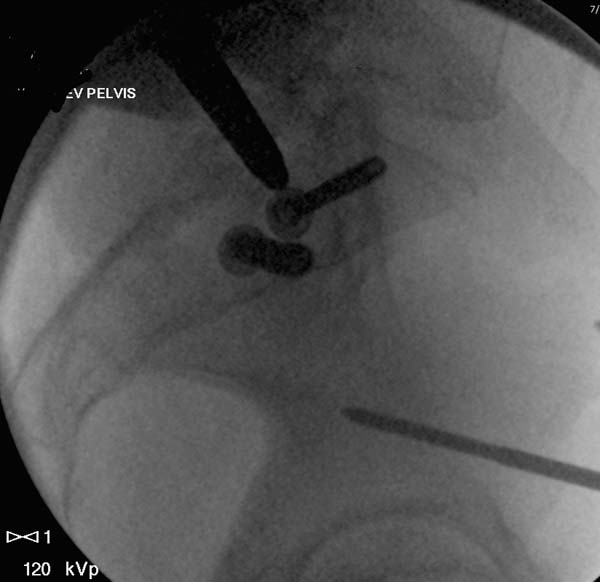

Большое спасибо всем Вам за помощь! Вчера прооперировали пациентку. Выполнили закрытую репозицию левой половины таза на тракционном столе под контролем ЭОП, закрытая фиксация левого КПС двумя каннулированными винтами. Учитывая удовлетворительное стояние отломков лонной и седалищной костей справа, а так же удовлетворительную ширину лона передние отделы стабилизировали системой ЦИТО

Послеоперационные КТ прилагаются

Винты введены в S1

Вроде бы все удалось. хорошо, что фрагмент (как выяснилось из КТ оказался небольшим), но для оценки лучше выкладывать рентген в стандартных проекциях